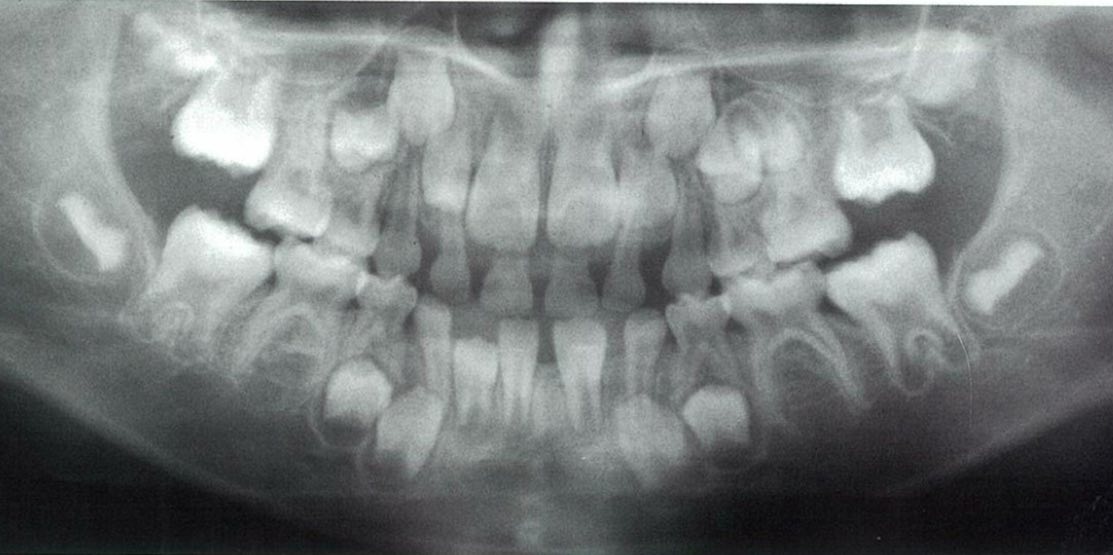

6歳の男児。定期診査を希望して来院した。来院時のエックス線写真を別に示す。

適切な所見はどれか。2つ選べ。

a Hellmanの歯齢はⅢA期である。

b 下顎切歯が1歯不足している。

c 犬歯の歯冠の位置は正常である。

d 下顎第二小臼歯が1歯不足している。

e 第一大臼歯の歯根形成は遅延している 。

正答 b,c

スクリーンショット 2017 01 31 11 14 40

以上を踏まえて問題のレントゲンを見てみると、、、上下6が萌出途中で、噛み合っていませんよね!ということで、これはⅢAになれていないので、ⅡCだと一発で判断することができます!

実は、国家試験の正答は間違っています。選択肢の「d 下顎第二小臼歯が1歯不足している。」が、誤答肢になっていますが、これは実は正しいです。パノラマをよく見てみると右下5の歯胚が薄くですが、でき初めています。この感じだと左下5も今後でてくる可能性は十分にあります。

御存知の通り、先天欠如の多い歯種は「8」「5」「2」ですね。それぞれ、「大臼歯」「小臼歯」「切歯」でもっとも遠心にある歯は退化傾向で、先天欠如が多いことで知られています。この問題のパノラマも「5」がその傾向にあり、下顎では歯胚の形成がすごく遅れており右下5のみ確認できます。上顎では左上5が正常に発生していますが、やはり右上5の歯胚は確認できません。

よって、本当はこの「d 下顎第二小臼歯が1歯不足している。」は微妙な選択肢で、最近の感じだと削除かこの選択肢も丸になる流れになると思います。クレームがついてもきちんとした反論はできないかと思わます。(一応、この内容は、大学の小児歯科の先生に確認とれていますし、ANSWERでは画像所見の欄にのみ指摘されています。)